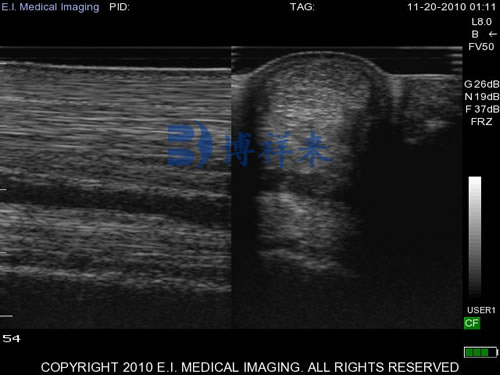

Longitudinal (sagittal) plane: Probe is aligned parallel to the tendon fibers.

Transverse (axial) plane: Probe is rotated 90° to capture cross-sectional views.

d. Image Acquisition: Adjust gain, depth, and focus to optimize the image. Tendons should appear as a linear, fibrillar pattern in longitudinal views and a round to oval, echogenic structure in transverse views. Identify any areas of hypoechogenicity (dark regions), fiber disruption, or swelling.